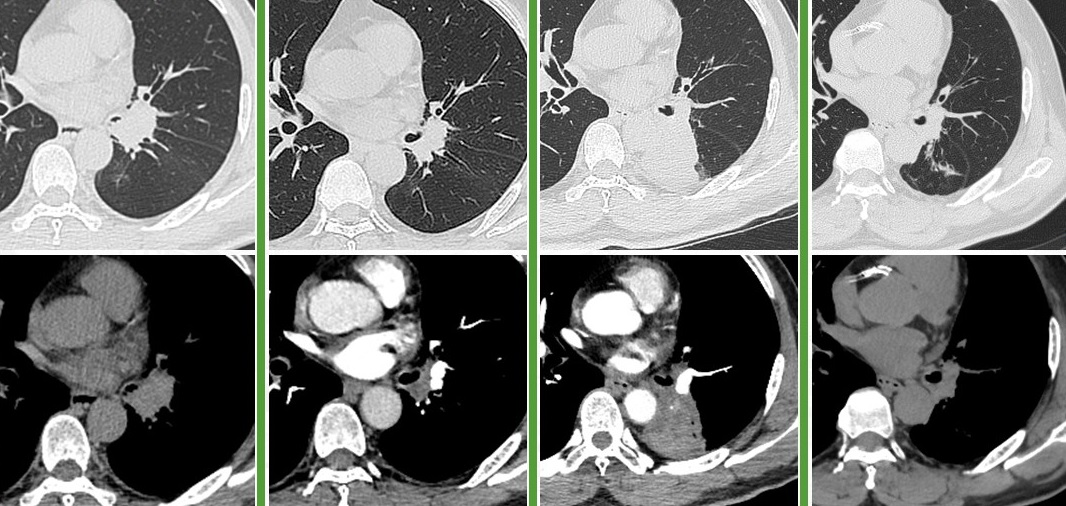

58岁,男,吸烟史40年×20支,2018.12体检发现左肺门占位,穿刺活检未见恶性成分。2019.12复查示左肺占位及纵隔淋巴较前增大,于我院行经食管超声镜下纵隔淋巴结穿刺活检,病理:小细胞癌。全身检查示左肺门、纵隔、肝门淋巴结转移,cT2bN2M1b IVA期广泛期。2020.1入组临床研究,予BGB-A317/安慰剂+EP方案化疗4周期,2020.4起行BGB-A317/安慰剂维持治疗,研究结束时揭盲,为BGB-A317组,继续免疫维持治疗至今(84周期)。截至2025.2.20

治疗小结:替雷利珠单抗+EP×4、替雷利珠单抗×84+,PFS 62个月+。

图:左起依次为基线、免疫联合化疗4周期后、末次随访